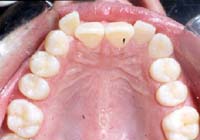

Treatment Time: 8 months

Aligners: 13 Upper, 13 Lower